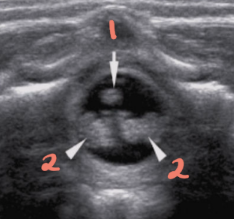

1

spinous processes

2

subarachnoid/dural layer

3

subarachnoid space filled with CSF

4

posterior margin of spinal cord

5

spinal cord with central echo complex

6

anterior margin of the spinal cord